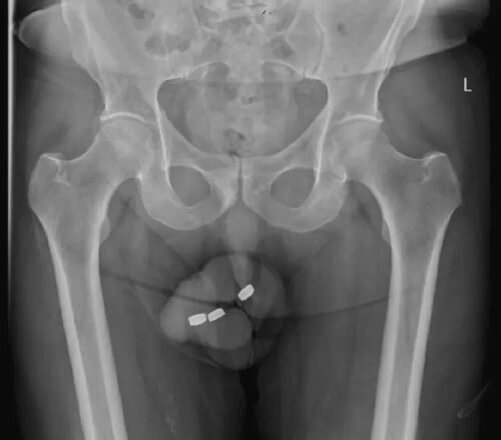

Врачи не ожидали, что к ним явится 73-летний пациент, который признается в том, что засунул в свой половой орган три круглых батарейки (их ещё называют «таблетками»).

Испуганный мужчина рассказал, что уже не в первый раз занимается подобными сексуальными экспериментами, и всё проходило благополучно, но на сей раз батарейки застряли. Выждав сутки, пожилой незнакомец отправился за медицинской помощью.

Несмотря на то, что элементы питания довольно быстро извлекли, проблемы оказались серьёзнее, чем все думали. Через несколько дней мужчина вернулся в больницу с жалобами на отёк полового органа и неприятные выделения. Опасения врачей о том, что у пациента развилась обширная степень некроза, оправдались — и бедолаге пришлось удалить часть мочеиспускательного канала. Всё-таки батарейки оказались совсем не предназначены для эротических игр.